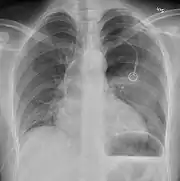

Chest X-ray

A plain chest radiograph, ideally with the X-ray beams being projected from the back (posteroanterior, or "PA"), and during maximal inspiration (holding one's breath), is the most appropriate first investigation.[25] It is not believed that routinely taking images during expiration would confer any benefit.[26] Still, they may be useful in the detection of a pneumothorax when clinical suspicion is high but yet an inspiratory radiograph appears normal.[27] Also, if the PA X-ray does not show a pneumothorax but there is a strong suspicion of one, lateral X-rays (with beams projecting from the side) may be performed, but this is not routine practice.[14][18]

Anteroposterior inspired X-ray, showing subtle left-sided pneumothorax caused by port insertion

It is not unusual for the mediastinum (the structure between the lungs that contains the heart, great blood vessels, and large airways) to be shifted away from the affected lung due to the pressure differences. This is not equivalent to a tension pneumothorax, which is determined mainly by the constellation of symptoms, hypoxia, and shock.[13]

The size of the pneumothorax (i.e. the volume of air in the pleural space) can be determined with a reasonable degree of accuracy by measuring the distance between the chest wall and the lung. This is relevant to treatment, as smaller pneumothoraces may be managed differently. An air rim of 2 cm means that the pneumothorax occupies about 50% of the hemithorax.[14] British professional guidelines have traditionally stated that the measurement should be performed at the level of the hilum (where blood vessels and airways enter the lung) with 2 cm as the cutoff,[14] while American guidelines state that the measurement should be done at the apex (top) of the lung with 3 cm differentiating between a "small" and a "large" pneumothorax.[28] The latter method may overestimate the size of a pneumothorax if it is located mainly at the apex, which is a common occurrence.[14] The various methods correlate poorly but are the best easily available ways of estimating pneumothorax size.[14][18] CT scanning (see below) can provide a more accurate determination of the size of the pneumothorax, but its routine use in this setting is not recommended.[28]